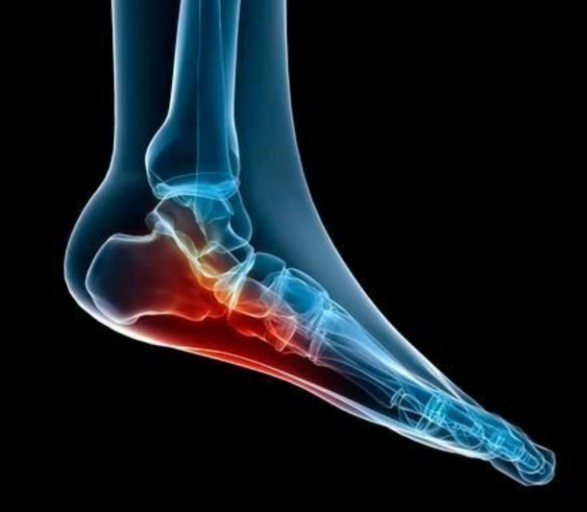

초기에는 밤에만 불편함을 느끼다가 점점 지속 시간도 늘어납니다.3. 족저근막염

발바닥 통증의 대표 질환으로,

발뒤꿈치에서 발바닥 전체로 이어지는 근막에 염증이 생기며

걷거나 서 있을 때 발바닥이 뜨겁고 찌릿한 통증을 유발합니다.

특히 아침에 첫 발을 디딜 때 더 아픈 경우가 많아요.